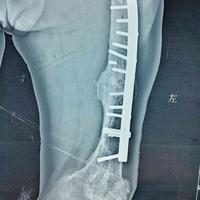

男性患者,跟骨骨折,小切口微创钢板

男性患者,跟骨骨折,小切口微创钢板...